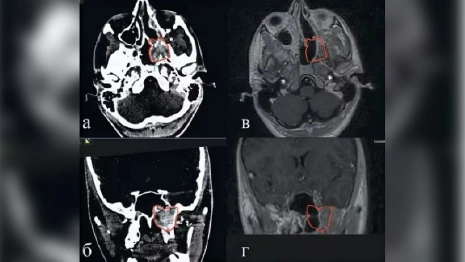

Врачи ЛОР отделения областной детской клинической больницы поставили серьезный диагноз ребенку – юношеская ангиофиброма основания черепа, сообщили в ОДКБ в четверг, 14 декабря. Хотя изначально 15-летний подросток жаловался на затруднение носового дыхания из одной половины полости носа и массивные кровотечения.

Юношеская ангиофиброма основания черепа – доброкачественная опухоль, встречающаяся в основном у мальчиков-подростков 9-19 лет. Опухоль агрессивно растущая, клинически проявляющаяся носовыми кровотечениями. Может привести к гибели пациента. Остановка таких кровотечений возможна только перевязкой сонных артерий.

Несмотря на доброкачественную морфологическую структуру, ЮАОЧ обладает выраженной способностью к инвазивному росту, разрушая кости основания черепа и проростая в полость черепа, крылонебную ямку, основную и гайморовы пазухи.